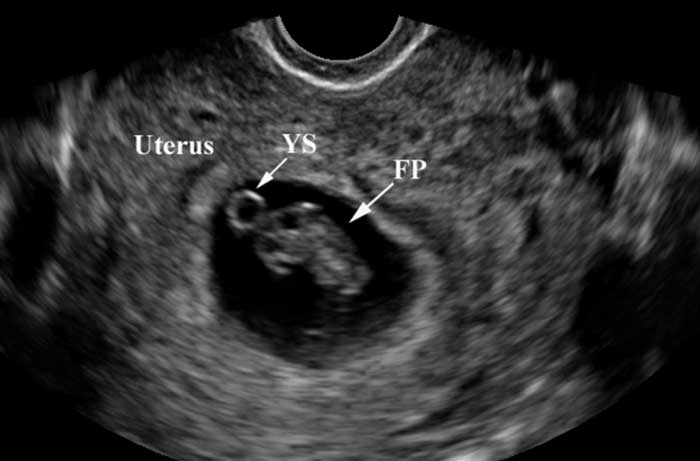

Túi noãn hoàng còn có tên gọi khác là Yolksac, được coi là cấu trúc hoàn chỉnh đầu tiên của thai nhi và sự xuất hiện của túi noãn hoàng là để chuẩn bị cho quá trình hình thành nhau thai.

Trong thời kỳ đầu mang thai, túi noãn hoàng có chức năng là nguồn cung cấp chất dinh dưỡng cho thai nhi phát triển. Đây là cấu trúc đầu tiên có thể nhìn thấy trong túi thai , bao bọc thai nhi đang phát triển và nước ối .

Túi thai trông giống như một vành trắng xung quanh một trung tâm rõ ràng. Nó có thể được nhìn thấy khi siêu âm qua âm đạo - trong đó đũa siêu âm được đưa vào âm đạo chứ không phải ấn vào bụng khi mang thai từ 3 đến 5 tuần. Túi noãn hoàng không thể nhìn thấy cho đến khi thai được khoảng 5,5 đến 6 tuần khi siêu âm ổ bụng.

Túi noãn hoàng cung cấp dinh dưỡng cho phôi thai phát triển cho đến khi nhau thai tiếp quản. Đó là lý do tại sao nó được đánh giá là một chỉ báo tốt về sức khỏe của thai kỳ.